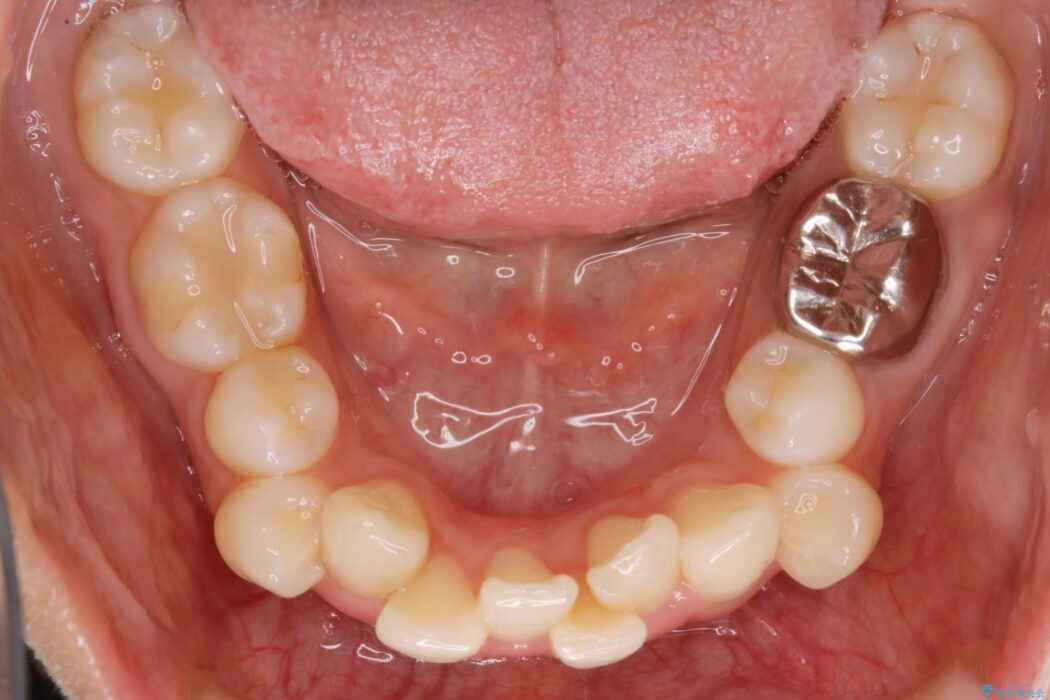

【20代女性】抜歯矯正で叢生をなおす

まず噛み合わせに問題が少ない奥歯の位置を極力変えないように上下左右4番目の歯を抜歯することで歯列矯正のためのスペースを確保し、空いた隙間で前歯の凹凸をきれいに並べていくこととしました。

また、ご要望がありマイクロインプラント治療もしています。

笑った時に見えるガタついていた見栄えが改善されて歯列弓もきれいな形に整い、患者様にはご満足いただけました。

従来の矯正治療では抜歯スペースなどの大きな移動のコントロールはワイヤー装置の方が適しているとされてきました。しかし、年々マウスピース装置の質が向上していることもあり、最近では抜歯した場合にマウスピース装置を使用することも増えてきました。

ですがそれを踏まえても、マウスピース装置だけできれいな歯並びへ抜歯矯正できる症例は確実に増加傾向にあると思います。